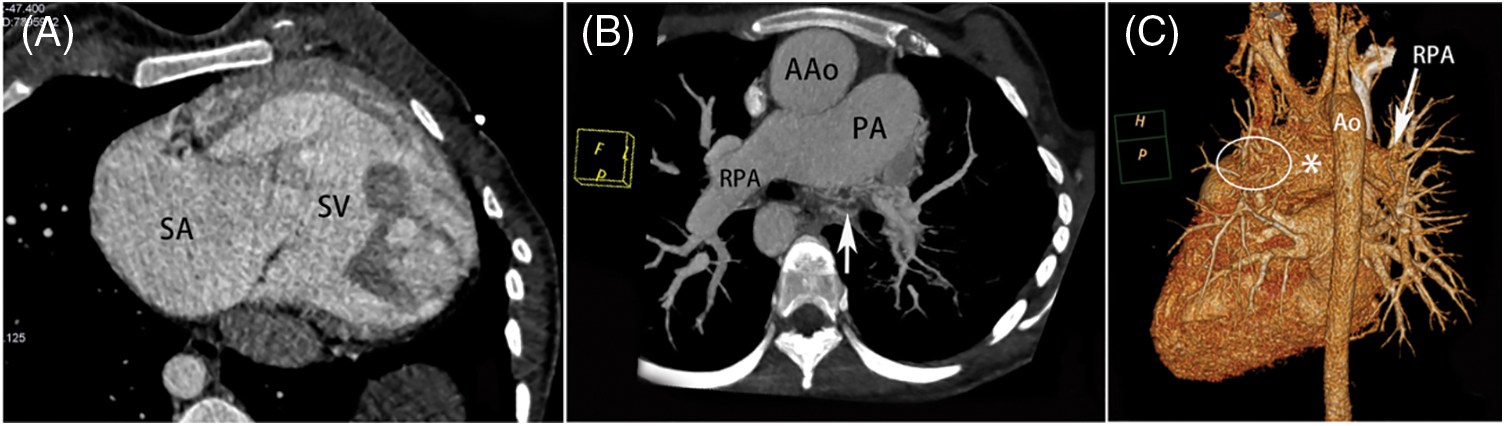

The various intracardiac and extracardiac malformations observed during surgery are detailed in Table 2. In terms of intracardiac malformation, patients with SV are most likely to be associated with atrial septal defect (33/75, 44.0%). In patients with SA, the most common abnormalities were pulmonary artery stenosis (12/24, 50.0%) and pulmonary valve stenosis (10/24, 41.7%) (Fig. 2). In SV patients, the top three malformations were patent ductus arteriosus (25/75, 33.3%), pulmonary artery stenosis (23/75, 30.7%) and right ventricular double outlet (20/75, 26.7%) (Fig. 3). In the patients with SA-SV, the incidence of pulmonary artery dilation (11/24, 45.8%), right aortic arch (10/24, 41.7%), right ventricular outflow tract stenosis (9/24, 37.5%), coarctation of aorta (9/24, 37.5%) were more pronounced (Fig. 4).

Figure 2: SA in a female aged 4 years. (A) The transverse plane of a SA with a ventricular septal defect (*). (B) Axial image shows the pulmonary trunk; LPA and RPA were stenosed (yellow arrow). The HV is thickened and located on the left side of DAo. (C) VR image shows the patent ductus arteriosus entering the PA from the Ao (white arrow). DAo = descending aorta, HV = hemiazygos vein, VR = volume rendering, other abbreviations as in Fig. 1